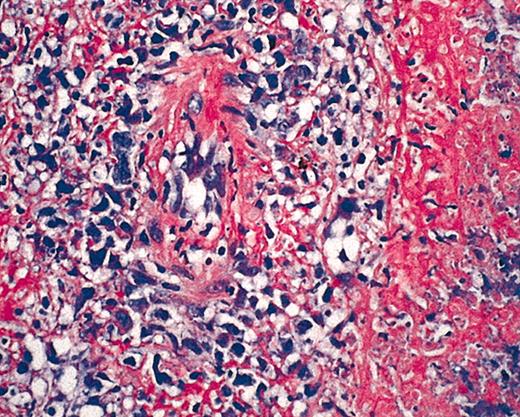

Hematoxylin and eosin (HE) staining of EBV+ B-cell diffuse large-cell lymphoma. Original magnification × 40.